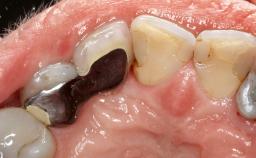

Ridge Preservation and Implant Placement for a Fixed Dental Prosthesis After a Car Accident

It is well known to clinicians that any removal of teeth will, over time, cause the dimensions of the alveolar ridge to be reduced by resorption of the bundle bone and by changes related to external modeling. This development is particularly evident in the crestal region with its thin buccal bone that consists of bundle bone almost entirely. The facial bone will rapidly resorb as blood supply from the periodontal ligament gets disrupted (Araújo and Lindhe 2005). There is no reason why traumatic tooth loss should not have the same consequences. It takes more than achieving implant osseointegration for a treatment outcome to be considered successful. No deficiency of bone or soft tissue is acceptable when an ideal esthetic outcome is the goal. Several articles (Sanz and coworkers 2011; Vignoletti and coworkers 2011) have reported on techniques of improving the alveolar ridge for implant treatment, notably focusing on protecting tissues from resorption.